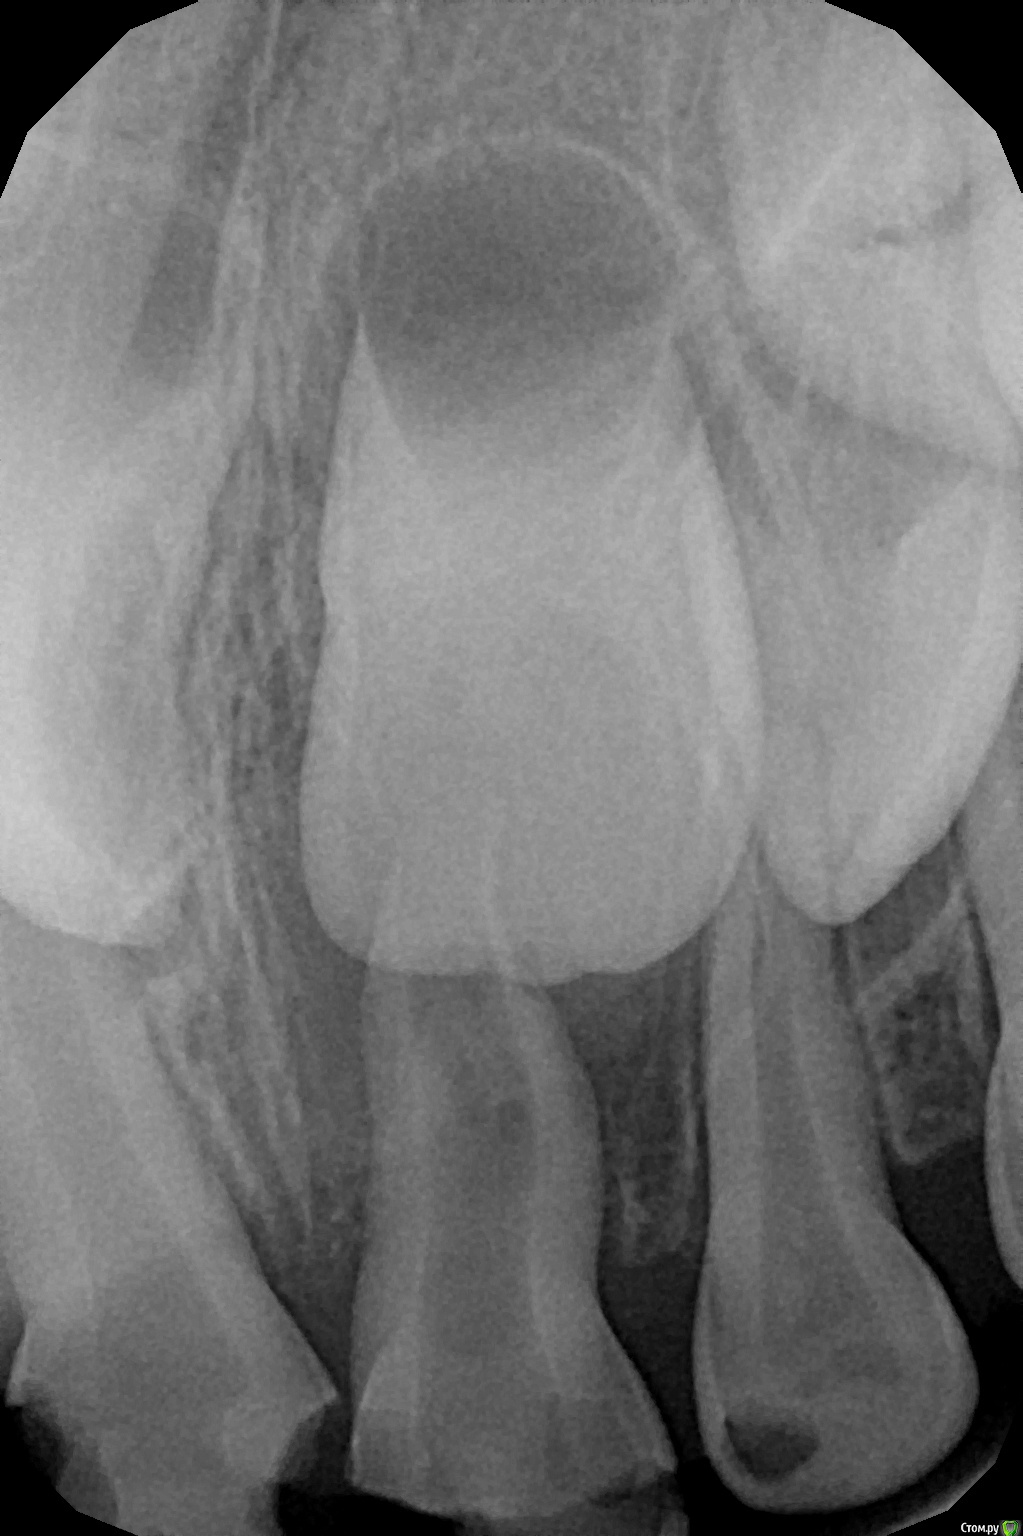

crown Опубликовано 25 июня, 2016 Поделиться Опубликовано 25 июня, 2016 Сегодня лечил 55. У меня возникло 2 вопроса. 1. На медиальном корне апикальный периодонтит, или это все пришло с бифуркации и малой кривизны? 2. МБ2 нужно искать, он вообще бывает в молочных? Ссылка на комментарий

Джима Опубликовано 25 июня, 2016 Поделиться Опубликовано 25 июня, 2016 1. crown, а какая, по большому счёту, разница?2. есть очень часто. если могу расковырять - расковыриваю, если не могу - значит, не судьба. у них кроме мб2 ещё много чего есть. Ссылка на комментарий

crown Опубликовано 25 июня, 2016 Поделиться Опубликовано 25 июня, 2016 1. crown, а какая, по большому счёту, разница?2. есть очень часто. если могу расковырять - расковыриваю, если не могу - значит, не судьба. у них кроме мб2 ещё много чего есть.Ну как, если инфекция в апикальной трети то нужно полностью проходить канал, а не на 2\3 как мы обычно делаем. Просто пропущенный мб2 в шестерке периодонтитной дает о себе знать со временем, т. к. там все таки есть инфекция. Ссылка на комментарий